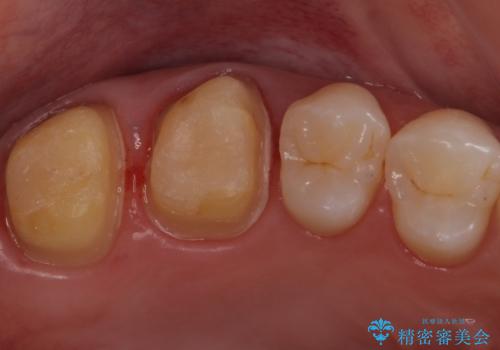

- 銀歯を白くしたいとのことで来院されました。

詰め物が覆っている面積が大きいため、強度を考慮してセラミックインレーではなくクラウンでの修復処置を進めていきます。